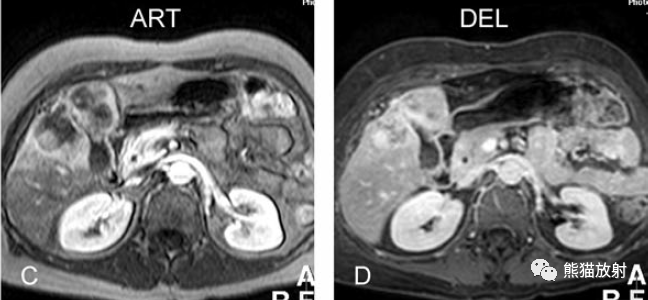

膽囊癌。A~D圖:上方層面,表現(xiàn)如上所述,形成腫物侵及肝臟。E、F圖:下方層面示膽囊壁不規(guī)則增厚,明顯不均質(zhì)強(qiáng)化。

另一例膽囊癌,T2WI及增強(qiáng)延遲期顯示膽囊壁不均勻增厚并明顯強(qiáng)化。